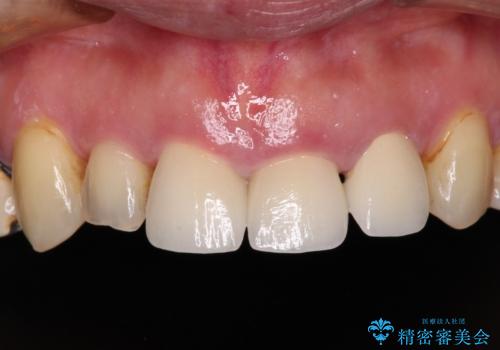

反対咬合や欠損を治療したい インビザライン矯正とオールセラミックブリッジ

虫歯治療や欠損補綴治療も必要でしたが、前歯が反対咬合であったので、セラミッククラウンやブリッジによる治療と並行して矯正治療を提案しました。